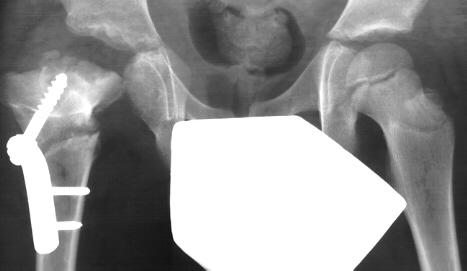

• Radiographs

• recommended views

• AP and frog-leg lateral pelvic x-rays, if hips can be put in frog leg position.

• findings

• may be normal, especially in early stages of disease

• widening of the joint space

• in infants, prior to ossification of the femoral head, widening of joint space can be seen by lateral displacement of the proximal femur

• this is a sign of significant pus in joint

• subluxation

• dislocation

• bone lesions

• may see bone involvement with associated osteomyelitis

• Femoral head destruction

• complete destruction of the femoral head and neck, easily visible on x-ray

• salvage operations exist including varus/valgus proximal femoral osteotomies